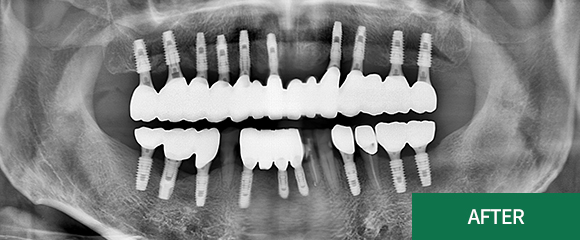

전악(전체) 임플란트

CASE 1